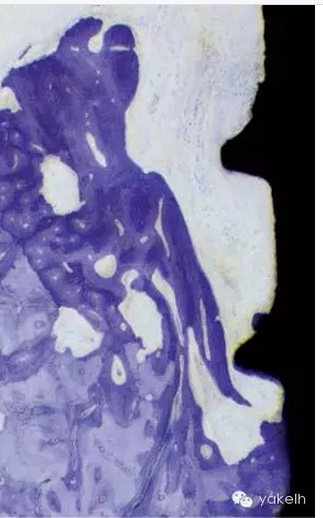

圖7.5 種植體周圍炎。(c)進(jìn)展期種植體周圍炎的病變。

¤¤其他研究組的研究人員在猴模型上通過絲線結(jié)扎導(dǎo)致菌斑積聚誘導(dǎo)出種植體周圍炎和牙周炎,并且與通過自然菌斑積聚誘導(dǎo)的兩種疾病的發(fā)生過程進(jìn)行比較。絲線結(jié)扎導(dǎo)致菌斑積聚誘導(dǎo)的天然牙周圍的臨床指標(biāo)如菌斑指數(shù)、牙齦指數(shù)、牙周袋深度和附著喪失的增加與絲線結(jié)扎導(dǎo)致菌斑積聚誘導(dǎo)的種植體周圍炎位點(diǎn)的臨床指標(biāo)的增加幅度一致。8個(gè)月后,附著喪失接近3.5mm,而在同樣的時(shí)間內(nèi)僅暴露在自然菌斑積聚的種植體的附著喪失不超過0.5mm。絲線結(jié)扎導(dǎo)致菌斑積聚誘導(dǎo)的牙周圍鑒定出的微生物群也與絲線結(jié)扎導(dǎo)致菌斑積聚誘導(dǎo)的種植體周圍的微生物群相同。此外,8個(gè)月后兩種病損通過組織學(xué)分析表現(xiàn)極為相似,且出現(xiàn)了骨內(nèi)缺損(圖 7.5)。數(shù)字減影成像術(shù)(DSR)顯示,絲線結(jié)扎導(dǎo)致菌斑積聚誘導(dǎo)的牙和種植體周有骨密度的喪失和骨內(nèi)病損的發(fā)展,而在整個(gè)實(shí)驗(yàn)階段自然菌斑積聚的種植體周牙槽骨的高度和密度沒有顯著改變。因此,這就意味著重度菌斑積累和一個(gè)足夠長的時(shí)間可以發(fā)展成為感染,病菌會(huì)逐漸侵襲到種植體周圍的支持組織就像在牙周一樣。然而,不是所有的種植體周圍黏膜炎位點(diǎn)都會(huì)發(fā)展成為種植體周圍炎,就像不是所有的牙齦炎位點(diǎn)都會(huì)發(fā)展成牙周炎一樣。

¤¤對(duì)實(shí)驗(yàn)狗組織樣本的組織病理學(xué)檢查顯示,牙周位點(diǎn)和種植體位點(diǎn)炎癥病損的大小和位置明顯不同。在牙周位點(diǎn),病損和牙槽骨間會(huì)被非炎癥性的結(jié)締組織區(qū)隔離,而種植體周圍組織病損在大多數(shù)情況下卻會(huì)擴(kuò)展和侵入牙槽骨的骨髓腔。

¤¤我們可以得出的結(jié)論是牙周組織和種植體周圍組織的炎癥的擴(kuò)散類型不同。菌斑相關(guān)的牙周炎病損會(huì)被局限在結(jié)締組織中,而種植體周圍的病損會(huì)侵入牙槽骨。與牙周組織相反,在種植體周圍組織,進(jìn)展的、菌斑相關(guān)的病損似乎很難被局限以消除,可以擴(kuò)展到邊緣的骨組織內(nèi),進(jìn)一步發(fā)展最終導(dǎo)致種植體失敗。用狗模型進(jìn)一步研究,觀察不同時(shí)期的組織破壞,已經(jīng)證實(shí)這個(gè)結(jié)論。